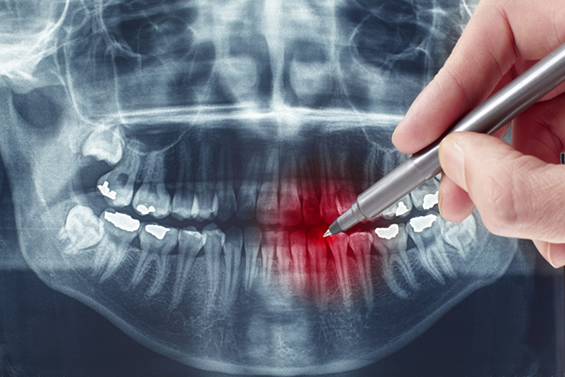

Radiografias Panorâmicas Digitais

É indicada para grandes áreas patológicas problemas da ATM, desvio de septo nasal, extrações dos terceiros molares (dente do siso), verificações de crescimento e desenvolvimento na ortodontia e odontopediatria, fraturas da mandíbula, para diagnóstico geral inicial e acompanhamentos de tratamentos, proporcionando também uma visão ampla das condições anatômicas da face.